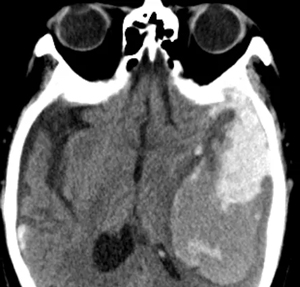

術(shù)后次日,程大爺清醒, 能認(rèn)識(shí)周圍的人,可以簡(jiǎn)單的發(fā)音,癥狀明顯好轉(zhuǎn),再次復(fù)查CT時(shí),血腫較術(shù)前明顯減少,未見新鮮出血。

術(shù)后3天復(fù)查CT,遂拔出引流管。術(shù)后7天,患者可在床邊進(jìn)行肢體活動(dòng),言語(yǔ),吞咽功能基本不受影響。

(術(shù)后一周)